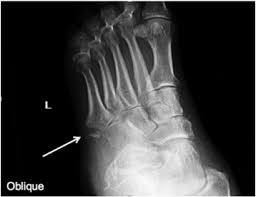

March fracture is also called ___ and looks like ?

stress fracture

avulsion fracture

ligament tears off a small part of bone